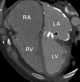

Dysfunctional prosthetic mitral valve

An artificial heart valve is a one-way valve implanted into a person's heart to replace a valve that is not functioning properly (valvular heart disease). Artificial heart valves can be separated into three broad classes: mechanical heart valves, bioprosthetic tissue valves and engineered tissue valves. [Source: Wikipedia ]